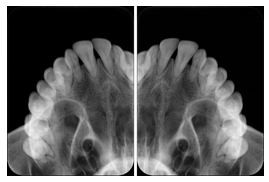

2 Occlusal Vertical Maxilla A Dental Image Layout

DL-C001A

Reference: DL-C001-U1L0

Reference: DL-C001-U2L0

00

Occlusal

18, 17, 16, 15, 14, 13, 12, 11, 13, 12, 11

01

21, 22, 23, 24, 25, 26,27, 28

2 Occlusal Vertical Mandible A Dental Image Layout

DL-C002A

Reference: DL-C002-U0L1

Reference: DL-C002A-U0L2

10

48, 48, 47, 46, 45, 44, 43, 42, 41

11

31, 32, 33, 34, 35, 36, 37, 38

2 Occlusal Horizontal Maxilla A Dental Image Layout

DL-C003A

Reference: DL-C003-U1L0

Reference: DL-C003-U2L0

18, 17, 16, 15, 14, 13, 12, 11, 13, 12, 11, 21, 22, 23, 24, 25, 26,27, 28